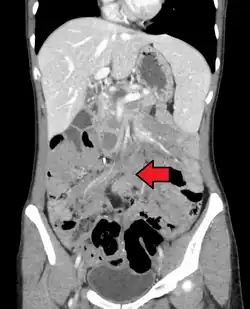

Desmoid tumor as seen on CT scan

MRI or CT imaging scans are commonly used for monitoring.[47][1]